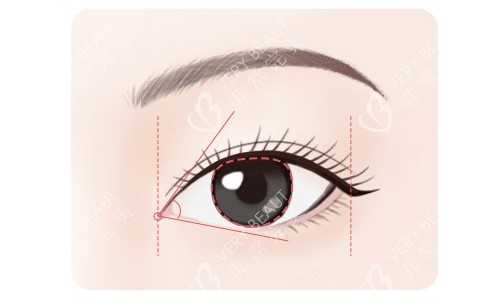

王博谦医生会在术前与患者进行深入沟通,了解患者的需求和期望。然后,根据患者的眼部基础条件、面部轮廓和个人外形,为其设计出较适合的双眼皮方案。无论是自然款、欧美风格款还是新月款,他都能精密把握,让双眼皮与面部整体相协调。

在手术过程中,王博谦医生手法轻柔、操作精细,能较大程度减少对眼部组织的损伤,降低术后肿胀和疼痛的程度,缩短修复时间。他还擅长运用小创口技术,使双眼皮线条流畅自然,宛如天生。